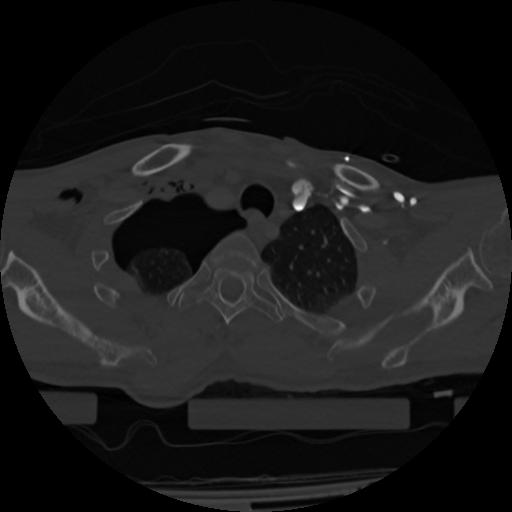

22 ANGIO,CE,Vol,0.5,ANGIO,,